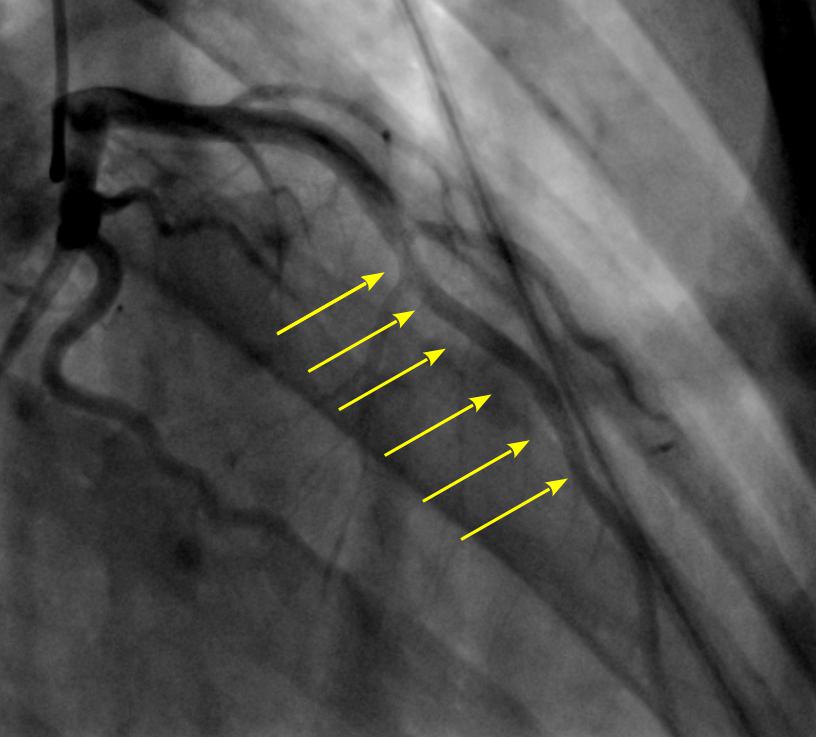

На рисунке приведена коронарография пациента после операции. |

«Обычным доступом при этой операции является срединная стернотомия (рассечение грудины). У данного пациента была выполнена супракоронарная миотомия через минидоступ (передняя левосторонняя миниторакотомия). По результатам контрольных послеоперационных исследований признаков компрессии артерий сердца не выявлено», — отмечает хирург, выполнивший операцию, заведующий отделением сердечно-сосудистой хирургии № 3 В. К. Гребенник.

«Коронарные сосуды в норме находятся на поверхности сердца — они окутывают его сеточкой, находясь на поверхности, не проходя глубоко в мышцы. А тут часть сеточки была под мышечным мостиком. Данная врожденная патология проявилась с ростом мальчика и увеличением мышечной массы сердца. Это очень редкое заболевание — за 31 год работы детским кардиологом я впервые столкнулась с таким диагнозом у ребенка. У взрослых пациентов он встречается, хотя тоже не часто. Хирурги Центра Алмазова удалили мостики, сжимавшие нормально сформированные коронарные сосуды. После операции, выполнив контрольную коронарографию, врачи увидели нормальное коронарное русло без сужения просвета во время сокращения сердца», — рассказывает лечащий врач Татьяна Николаевна Макушкина.